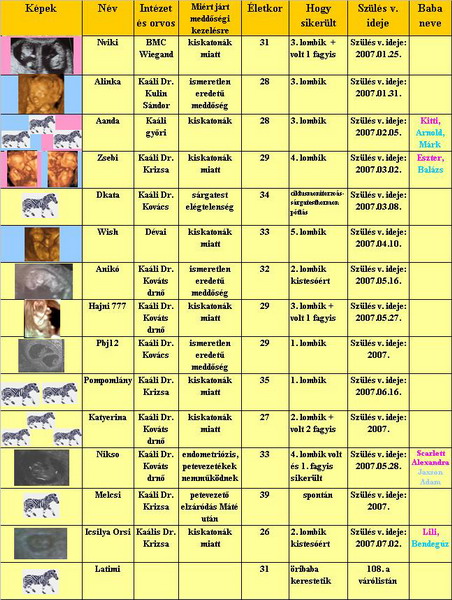

Sziasztok

Sziasztok

Erika